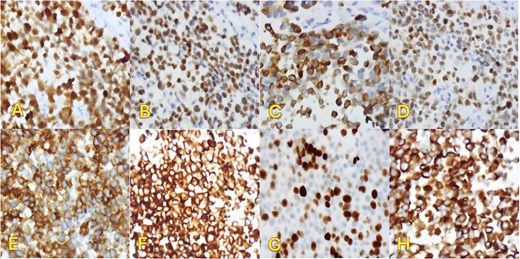

An fluorodeoxyglucose positron emission tomography-computed tomography (PET-CT) scan showed highly suspicious metabolically active malignancy and associated metastasis involving the cluster of right upper lobe pulmonary nodules, right-sided pleural effusion/thickening, right-sided pleural nodularity extending along the fissure, multiple mediastinal lymph nodes and an avid lymph node within the post-thyroidectomy bed (Fig. 1c). As the patient was not a surgical candidate, the interventional radiologist performed an ultrasound-guided core biopsy, and pleurodesis with doxycycline was done through the pigtail catheter. The patient was discharged a week later with a stable X-ray and on Lovenox medication. His serum LDH level was elevated by 58 points, and Calcitonin was in the normal range. H&E staining revealed malignant cells with variable size, nuclear irregularity, and eosinophilic cytoplasm, indicating cancerous tissue within the pleura (Fig. 2). However, the exact primary origin of these malignant cells remained undetermined. Extensive immunostaining was performed to identify the source of the malignancy. Tumor cells were strongly positive for S100, SOX10, Melan-A, MITF, CD99, BCL2, WT, and Ki 67 at 40%–50%, confirming a diagnosis of metastatic melanoma (Fig. 3).

Immunohistochemical staining (×400). Pleural biopsy was strongly positive for (A) S100, (B) SOX10, (C) Melan-a, (D) MITF, (E) CD99, (F) BCL2, (G) Ki67, and (H) WT1.